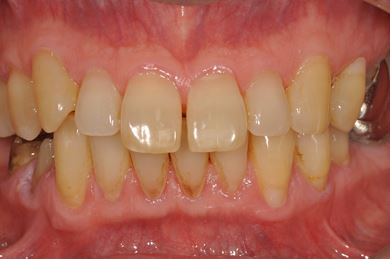

| 性別/年齢 | 男性 / 57歳 | ||||||||||||||||||||||||||||||||

| 主訴 | 右奥歯のブリッジが取れ、支柱の2本の歯が痛むため、インプラント治療を希望。 | ||||||||||||||||||||||||||||||||

| 治療内容 | インプラント2本、ハイブリッドセラミック2本 | ||||||||||||||||||||||||||||||||